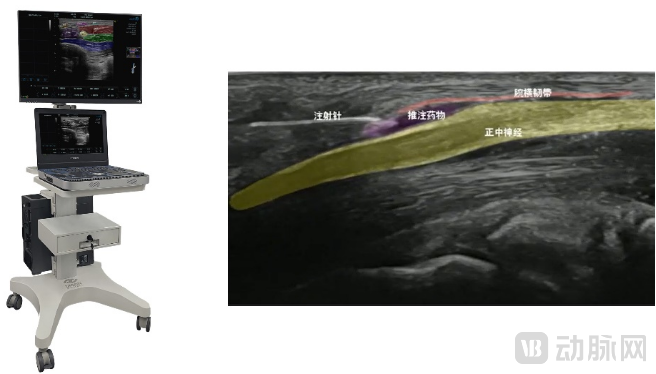

视知觉的首推产品是肌骨超声实时动态人工智能(AI)辅助诊疗系统——智影,是业内首款集教学培训、辅助诊断、辅助治疗于一体的肌骨超声AI产品。围绕肌骨超声特定需求,陆续开发了活体解剖结构实时动态可视化、健患侧生理特征参数对比、彩色血流指数检测、标准切面参考及解剖提示等重要功能。目前,产品已完成肩、肘、腕、髋、膝、踝、颈等AI模块,胸、腰、骶、头面、胸壁等正在快速开发当中,以及,针对疼痛科、麻醉科的精准诊疗模块,为医生提供一个全面、高效的肌骨超声诊疗平台,明显改善学习曲线。产品已适配市场主流高端超声设备以及国产主要便携式超声设备,可加速广大医院开展肌骨超声诊疗的能力。

视知觉肌骨超声AI(智影)及效果